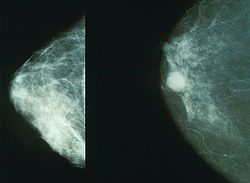

خبرني - ذكرت دراسة جديدة أن كبر الثديين قد يكون مؤشراً على احتمال الاصابة بمرض سرطان الثدي عند النساء في منتصف العمر وقال الدكتور نورمان بويد من معهد كامبيل العائلي لابحاث سرطان الثدي في مستشفى الأميرة مرغريت في تورنتو، إن الفحص بالرنينن المغناطيسي الذي أجري لمريضاتٍ أظهر وجود علاقة قوية بين كبر الثديين والاصابة بسرطان الثدي، عند النساء في منتصف العمر وكذلك عند نساء بلغن مرحلة الشيخوخة.

ونصح بويد في الدراسة التي نشرت في مجلة "لانسيت أنكولوجي" لعلم الأورام النساء بالخضوع للفحص بالرنين المغناطيسي، الذي وصفه بأنه تقنية أقل أذى للمرأة، بدل الأشعة السينية (أشعة أكس) في مرحلة مبكرة للكشف عن أية أورام في الثديين.